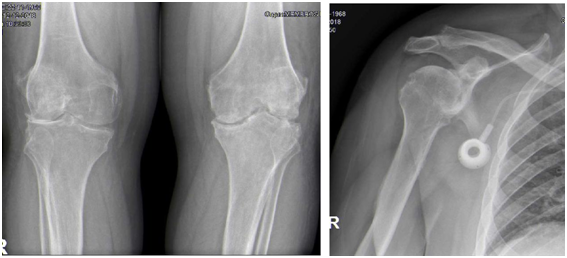

A 46-year-old man presents in our emergency with fever, severe left knee pain with inflammatory signs, within one week of evolution (Figure 1). He had sigmoid colon adenocarcinoma, submitted to left hemicolectomy (February 2013), retroperitoneal metastasectomy (January 2014), and chemotherapy. An intraarticular infiltration with steroids was performed two weeks before on that knee. An initial white blood cell count was slightly elevated at 11.3/mL with elevated C-reactive protein of 160.1 mg/L. A possible septic arthritis was diagnosed and it was performed evacuated arthrocentesis for microbiologic analysis and joint lavage with hematopurulent content output. He started empiric treatment with intravenous flucloxacillin 2g qds and gentamicin 240mg. No significant clinical improvements while awaiting results, underwent knee arthrotomy, joint lavage, extensive debridement and arthrolysis. During the surgery, it was found purulent content and dark pigmentation on bones and soft tissues (Figure 2). Postoperative microbiology samples reveal metecilin-sensible Staphilococcus aureus infection. It was made urine tests of alkaptonuria, that were positive. After maintaining the intravenous flucloxacillin for 2 weeks with good response, the treatment was shifted for oral with rifampicin, according to antibiogram. Besides antibiotic cycle, rehabilitation was also important for the treatment, and the patient improved his endurance with satisfying range of motion of the knee. After four years follow-up, the patient can walk 90 with crutches, with minor knee pain. He also presents complaints on both shoulders. In physical exam he has limitation on range of motion in knees (Figure 3) and shoulders. Radiologic findings show osteoarthrosis joints (Figure 4), but no additional treatments were done or proposed.

Overall, the incidence of ochronotic arthropathy in patients with alkaptonuria is low.2 Differential diagnosis must be done with ankylosing spondylitis and degenerative osteoarthosis.7 However, certain radiologic findings allow its differentiation, like unusual sites of joint involvement (severe glenohumeral joint disease in the absence of significant trauma, advanced changes in the sacroiliac joints and symphyseal joints), and joint-space loss with an unusual pattern (symmetrical joint-space narrowing in the hips and shoulders, and isolated lateral femorotibial loss of knee joint space) (Figure 4). Involvement of large peripheral joints usually occurs about 10 years after spinal changes.7 Darkening of the urine is a common diagnostic feature and should be considered in children even producing it unusually.2 Diagnosis can be confirmed using gas liquid chromatography, thin-layer chromatography, or enzymatic spectrophotometry to analyse the amount of homogentisic acid in the patient’s urine. Arthroscopy has been found to be an effective diagnostic tool in cases of suspected ochronosis.2

Figure 4 Radiologic findings showing osteoarthrosis joints: A. Bilateral Knee anteroposterior x-ray; B. Right Shoulder x-ray.